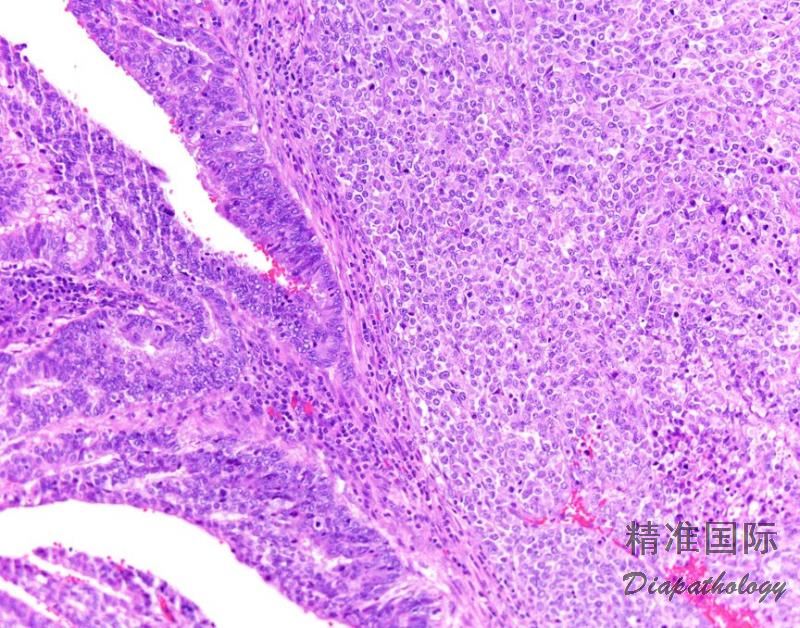

在未分化癌的背景上出现 FIGO 1 级或 2 级子宫内膜样癌成分。

3. 肿瘤细胞成片排列,没有明显的巢状或小梁状结构或腺腔形成;;

4. 肿瘤细胞黏附性差,小到中等大小,形态一致,类似高级别子宫内膜间质肉瘤、小细胞癌或浆细胞瘤,少数病例可见核多形性;

5. 细胞核深染,分裂像易见,大多数病例核分裂像>25/10HPF;

6. 在未分化癌背景上出现第二种成分,表现为 FIGO 1 级或 2 级子宫内膜样癌结构。